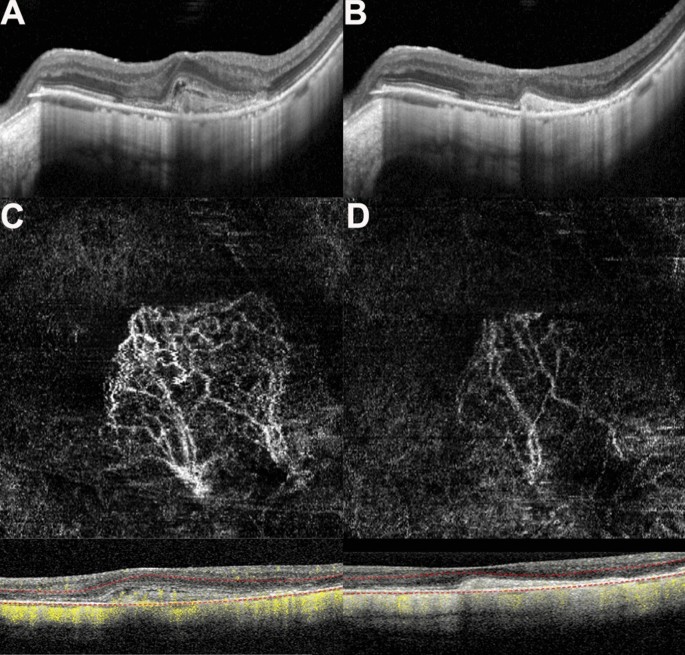

Before treatment, the morphological shape of the MNV in OCTA images was like a flower, fan, or small tree bud. Two subtypes of myopic MNV were distinguished10,11 on the basis of different characteristics in size and morphology: the well-organized larger “interlacing” pattern and the small, disorganized MNV “vascular loop” subtype (Figs. 3, 4). The intraobserver agreement was 95.2%. After conbercept injection, the small-diameter blood vessels of the MNV decreased, the intertwined small blood vessels decreased or even disappeared, and the main or larger-diameter blood vessels were still present, but blood flow was significantly reduced. The OCT and OCTA changes in a patient is shown in Figs. 3 and 4. The mean selected MNV area and blood flow area were 0.62 ± 0.81 and 0.22 ± 0.27 mm2, respectively, before treatment, and decresed to 0.23 ± 0.33 and 0.07 ± 0.08 mm2 (P = 0.04 for both), respectively, 1 month after conbercept treatment (Table 2).

(A,B) Optical coherence tomography (OCT) images of a patient with myopic macular neovascularization (mMNV) before and after receiving conbercept. Central macular thickness (CMT) decreased from 371.43 to 248.98 μm. The hyperreflective signal lesions in the outer layer of the retina shrank and the outer structure tended to normalize. (C,D) Optical coherence tomography angiography (OCTA) images of the patient before and after injection. (C) Presents a large-area, highly organized, interlaced high-flow MNV vascular network. It contains small capillary branches and nourishing blood vessels and is surrounded by a low-signal halo, showing a leafy tree crown or sea fan shape. One month after conbercept treatment, the MNV of (D) shows only nourishing blood vessels with larger diameters, the small blood vessels decreased or even disappeared, the blood vessels intertwined, and the blood flow was significantly reduced. The MNV areas in (C) and (D) are 2.69 and 1.08 mm2, while the blood vessel areas are 0.92 and 0.24 mm2, respectively.

The results of our study revealed that the average baseline vascular area of mMNV measured by OCTA was 0.62 ± 0.81 mm2, and the blood flow area was 0.22 ± 0.27 mm2. The vascular area of mMNV of our study is close to the finding by Miyata et al. (0.59 ± 0.56 mm2)23, which is significantly larger than the finding by Bruyere et al. (0.22 ± 0.27 mm2)10. Furthermore, we have distinguished two subtypes of mMNV similar to those of Bruyere et al., with different characteristics of size and morphology: a large, highly organized, interlacing high-flow network containing small capillary ramifications, bordered by a dark halo, with feeder vessel (Fig. 3) and a small, disorganized MNV “vascular loop” subtype, showing irregular blood flow and a small tree bud-shaped lesion composed of a small number of discontinuous linear branch blood flows(Fig. 4)10.

Previous studies reported the vacular remodeling of MNV after anti-VEGF therapy in nAMD on OCTA24,25. In nAMD, the pruning of smaller vessels occurred 24 h after anti-VEGF treatment, increasing and reaching the maximum flow regression between 6 and 12 days, followed by reproliferation (reopening or new sprouting of the vessels) after 20–50 days24. In another case series, the authors identified two types of MNV morphology progression in after anti-VEGF treatment: constant patterns, conserving their disorganized morphology with tiny capillaries and loops, are suggestive for immature MNV; however, changing patterns are subject to arteriolization with thicker dilated vascular trunks and the absence of tiny ramifications, ultimately suggestive for a mature neovascular lesion25. In patients with mMNV, a study analyzed the 1-month follow-up course after anti-VEGF treatment. mMNV were classified as irregular mass, referred to as tree-in-bud or a nearly round-shaped mass with a continuous ring around the lesion. At 1 month, changes were observed with decreased MNV size, narrowed lesion with the pruning of thinner peripheral blood flow, and decreased network density6. Similarly, in our study, the mean blood vessel area was 0.23 ± 0.33 mm2 and the mean blood flow area was 0.07 ± 0.08 mm2; both values significantly reduced compared with those of baseline (P = 0.04 for both) 1 month after intravitreal conbercept injection. OCTA images revealed that the capillaries and small-caliber feeder vessels were attenuated significantly after 1 month of conbercept treatment, which may have decreased the flow signals or caused these vessels to regress. However, the main central trunk vessel and large-caliber feeder vessels remained unchanged. These findings are similar to those of the study by Huang et al.26. Further studies are required to investigate the morphological changes in mMNV on OCTA, before and after treatment with anti-VEGF agents and the correlations between these changes and signs of neovascular activity.